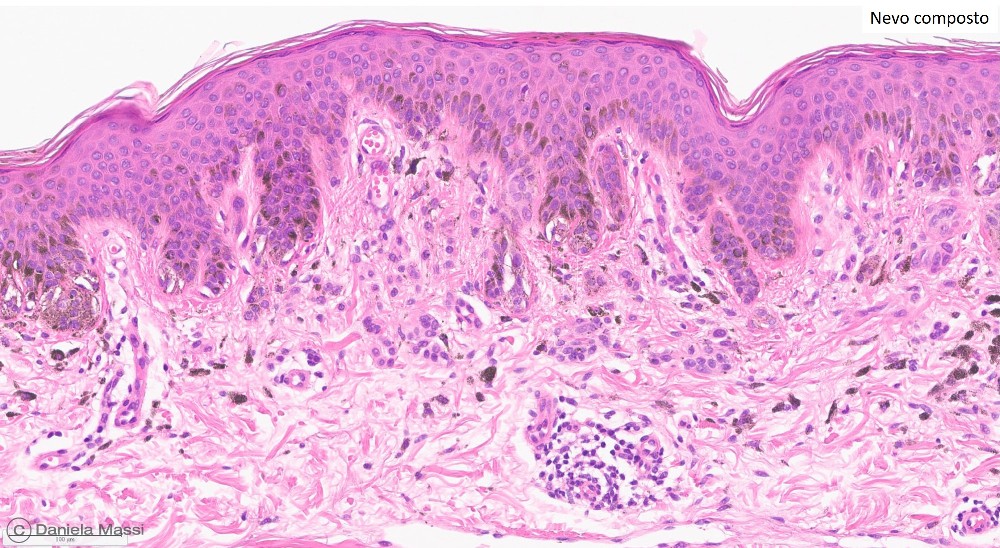

I nevi più comuni sono classificati istologicamente a seconda della loro prevalente localizzazione in relazione alla cute in: